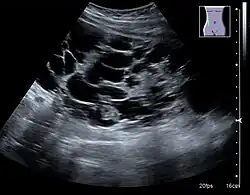

Peripelvic versus parapelvic cysts

Non-contrast CT (at left) showing peripelvic fluid accumulations, which may be hydronephrosis. CT urography (at right) reveals non-dilated calyces and pelvises. The fluid accumulations are thus peripelvic cysts.

Parapelvic cysts originate from around the kidney at the adjacent renal parenchyma, and plunge into the renal sinus. Peripelvic cysts are contained entirely within the renal sinus, possibly related to dilated lymphatic channels. When viewed on CT in absence of contrast, they can mimic hydronephrosis.[15] If symptomatic, they can be laparoscopically decorticated - removal of the outer layer or cortex.[16]